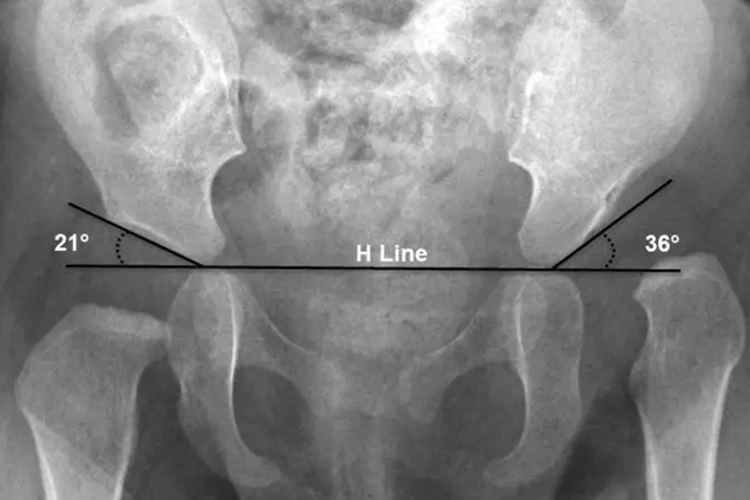

胯骨即髋骨,左右髋骨不对称可表现为髋关节屈曲、内收、内旋,或一侧髋骨倾斜、突出。

髋关节疾病,如髋关节脱位、髋关节发育不良和腰椎间盘突出等可能导致左右髋骨不对称。

外伤或者车祸导致髋关节后脱位时,患侧髋关节呈屈曲、内收、内旋畸形;先天性髋关节发育不良引起一侧或者双侧的髋关节脱位、半脱位;腰椎间盘突出症的患者由于腰椎侧弯,双侧的髋关节进行性代偿等原因均可导致左右髋骨不对称。